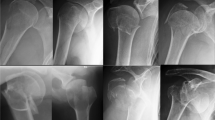

Illustration of fracture fixation of simple coronal shear fractures of the capitellum (Dubberley 2B) with two different fixation methods: 2A) Anteroposterior x-ray (left), lateral 3D CT scan (middle) and anteroposterior view (right) of two anteroposterior HCSs with additional anterior antiglide plate (group HCS + antiGP). 2B) Anteroposterior x-ray (left), lateral 3D CT scan (middle) and posteroanterior view (right) of posterolateral distal humerus locking plate (group PLP)

Two parallel 0.8 mm K-wires were placed in an anteroposterior direction into the capitellum perpendicular to the fracture line with about 1 cm distance in between. Screw length was measured with a cannulated depth gauge and partially threaded HCS with a 2.2 mm diameter (Speedtip CCS 2.2 mm, Medartis, Basel, Switzerland) were used. Screw length was chosen just 2 mm shorter than measured, to avoid penetrating the posterior cortex. The cartilage and subchondral bone of the first cortex was predrilled with a cannulated 1.8 mm drill. The self-drilling and self-tapping cannulated HCS screws were gently introduced with a screwdriver into a final position just about 0.5–1 mm below the cartilage level. After placement of two anteroposterior HCS (Speedtip CCS 2.2 mm, Medartis, Basel, Switzerland), additional fracture stabilization was performed using an anterior antiglide plate. Therefore, a 2.0 mm frame plate (Trilock, Medartis, Basel, Switzerland) was adjusted to the specific anatomy of each distal humerus to prevent the proximal dislocation of the capitellum. Care was taken to allow at least 120° of flexion in the radiocapitellar joint. The plate was fixed with three 2 mm bicortical proximal screws, directed in a posterolateral direction to avoid posterior screw impingement in the olecranon fossa. The medial and posteromedial fragments were additionally fixed with two separate 2.8 mm cortical screws placed in a lateromedial direction (Fig. 2A).

A posterolateral distal humerus locking plate (Trilock 2.8 mm, Medartis, Basel, Switzerland) was adjusted to the individual anatomy of the distal humerus. Initial fixation was performed with proximal 2.8 mm cortical screws. Afterwards, the fracture was fixed with three posteroanterior locking screws placed into the subchondral bone of the capitellum through the distal holes of the plate, perpendicular to the fracture line. The adequate length of the screws was chosen to a position 1 to 2 mm below the articular cartilage. The medial and posteromedial fragments were additionally fixed with two separate 2.8 mm cortical screws placed in a lateromedial direction, with the distal screw placed through the extension hole of the plate (Fig. 2B).